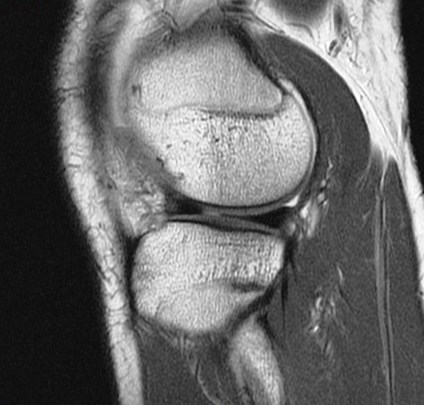

Figure 2 for case Unstable displaced lateral meniscus flap tear( RID2763 )

Figure 2

The flap is folded and displaced into the notch.

Unstable displaced lateral meniscus flap tear( RID2763 )